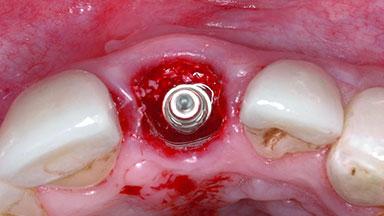

Replacement of a Failing Upper Left Central Incisor: Immediate Placement of an RC Bone Level Implant and Provisionalization

A healthy 23-year-old female patient was referred for a consultation on replacing tooth 21 with an implant-supported restoration. The patient had recently moved to the area and reported a history of endodontic and periodontal treatment for tooth 21. The tooth had been deemed non-restorable by her previous periodontist but since she was going to be moving, he recommended consulting to a dentist in her new city to continue her treatment. A review of her medical history yielded no significant findings and no known drug allergies. The analysis of her smile revealed a medium to high symmetrical smile line and a slightly discolored tooth 21.

Placement Protocol Immediate implant placement

Socket Morphology Single-root socket

Socket Integrity Damage to one or more bone walls

Bone Volume Damage to one or more socket walls